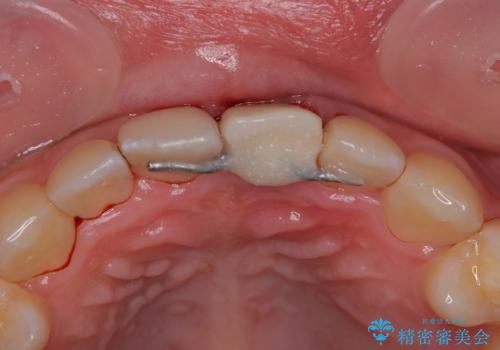

抜歯、インプラント埋入、仮歯の装着が同時に可能な1DAYインプラントを行いたいところでしたが、吸収による歯肉の炎症が著しいため、抜歯後に炎症が治まるまで待機し、極力早期にインプラント埋入を行うこととしました。

長い間歯肉が炎症を患っていたため、炎症改善後には歯肉がやや退縮した状態となっていました。

歯肉移植により歯肉形態を改善するプランも提案しましたが、十分な仕上がりとのことで、大変満足していただけました。